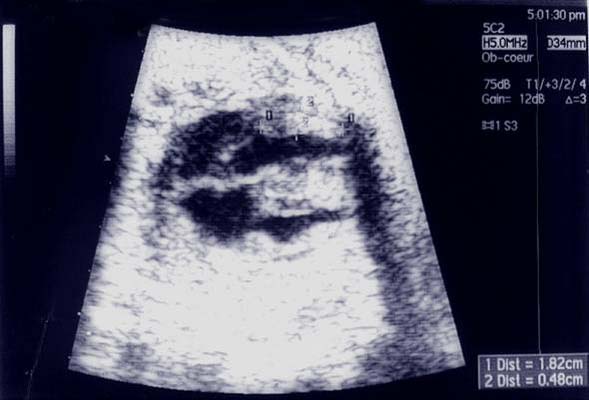

Epanchements péricardiques